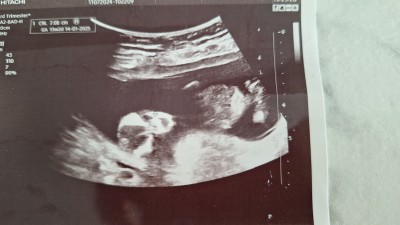

Kızlar 12 hafta usg cinsiyet tahmininiz varmi doktor söyledi ama çok emin olamadim belki anlayan birileri vardır

image